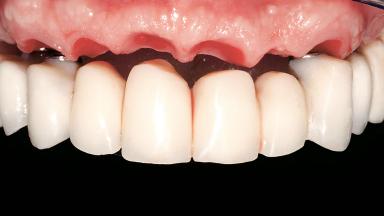

Immediate Loading of Six Implants in the Maxilla and Final Restoration with a Full-Arch CAD/CAM Zirconia FDP

A 63-year-old male patient was referred for a consultation and treatment of partial edentulism in the maxilla. The patient presented with residual anterior teeth and declined a partial removable prosthesis. He reported that the maxillary posterior teeth had been extracted due to mobility and periodontal disease two months before the consultation. The patient’s chief complaint was that his residual maxillary teeth were mobile and that he was unable to chew. The patient’s desire was a stable and comfortable fixed maxillary rehabilitation. The patient was a light smoker (fewer than 10 cigarettes/ day), and his medical history was without significant findings. He was not on any regular medication at the time of consultation. The extraoral examination revealed a normal physiognomy with a correct distribution of the facial thirds. The patient presented a low lip line, and the transition line between teeth and soft tissues was not exposed during a forced smile.

Lip Line No exposure of papillae Exposure of papillae Full exposure of mucosa margin

Esthetic Risk Medium

Occlusal Scheme/Issues Anterior guidance